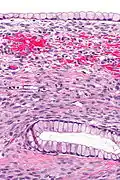

| Micrograph showing a mucinous cystadenoma of the ovary. H&E stain. | |

Mucinous cystadenoma is a benign cystic tumor lined by a mucinous epithelium. It is a type of cystic adenoma (cystadenoma).